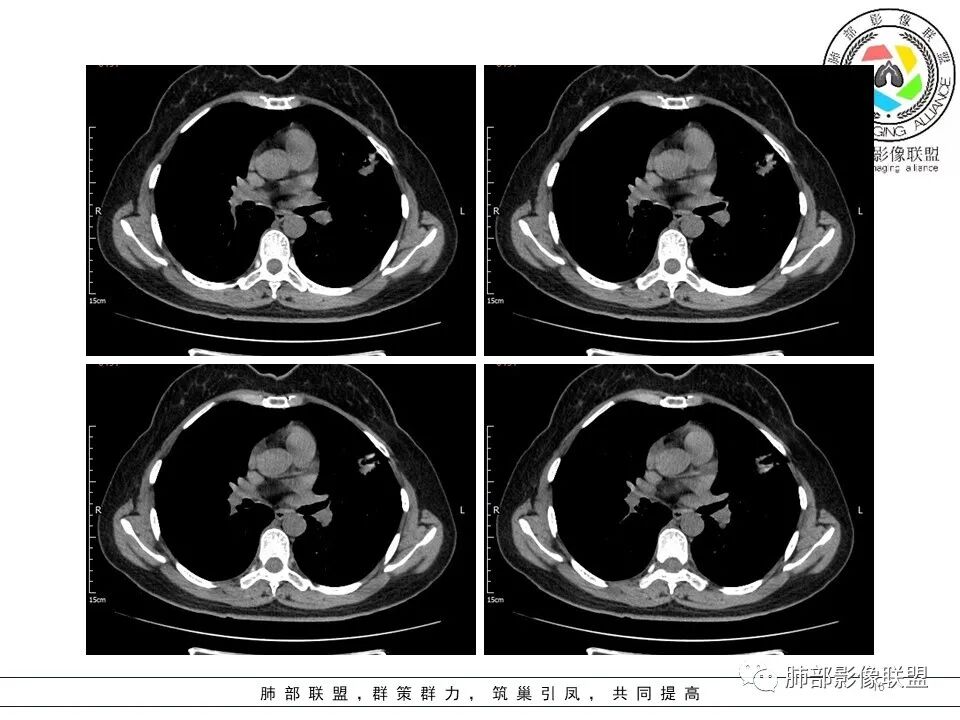

左肺上叶ggo,短毛刺,空泡征,6个月后复查病灶似变大,有轻度不均质强化,腺癌?胸膜下粟粒结节,无变化,良性?

分叶结节,内部结构杂乱,边缘板刷样毛刺,GGO边界清楚

胸膜牵拉

月牙铲?

常规要考虑腺癌

左肺上叶胸膜下不规则结节影,分叶、粗短毛刺,胸膜牵拉等,像个“刺头”。

未见钙化,也未显示液化坏死或空洞。

与支气管相关,但取层未能显示支气管进入情况。

1.病灶周围向几个方向膨出的边界清楚的磨玻璃影,这些磨玻璃影时隔几个月依然,几乎可以排除出血及一般的炎性改变。

2.病灶的胸膜牵拉线与其间病灶胸膜侧的磨玻璃边构成朝向胸壁的“月牙铲”结构,这种影像学表现某种程度上反映出病理学特征——病灶收缩+小叶间隔阻挡。

3.病灶实性密度区强化明显,这有助于我们区分一些其他类似病灶,如结核灶等!

4.邻近未见树芽征及卫星灶等。

结合临床,应当高度怀疑浸润性肺腺癌!